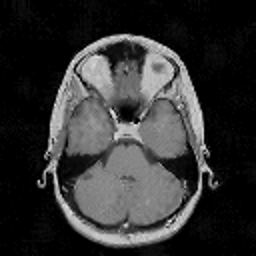

VII-C Experiments with real-life data

Reconstruction of real-life MRI images has been the next step in our comparative study. To this end, the data set of [19] have been used herein. The data were obtained at the University Hospital of Ghent and it is publicly available at http://telin.ugent.be/~sanja/Sanja_files/Software/MRIprogram.zip. The data contains a sagittal and an axial scan of a human brain, which are shown in Fig. 10 and Fig. 11, respectively.

The reconstruction results obtained for each of the tested images using the proposed and reference methods are shown in Subplots (b)-(f) of Fig. 10 and Fig. 11, respectively. From these figures, it can be seen that the proposed algorithms result in higher-contrast reconstructions of better visual clarity as compared to the reference approaches. The difference is particularly evident for the case of Fig. 11, where the proposed algorithms result in less noisy images, while exhibiting higher effective resolution and contrast.

Refer to caption

Figure 11: (a) Axial MRI scan; (b)-(f) Reconstruction results obtained using TVDN, WDN, GNLM, NLMS and NLMR, respectively.